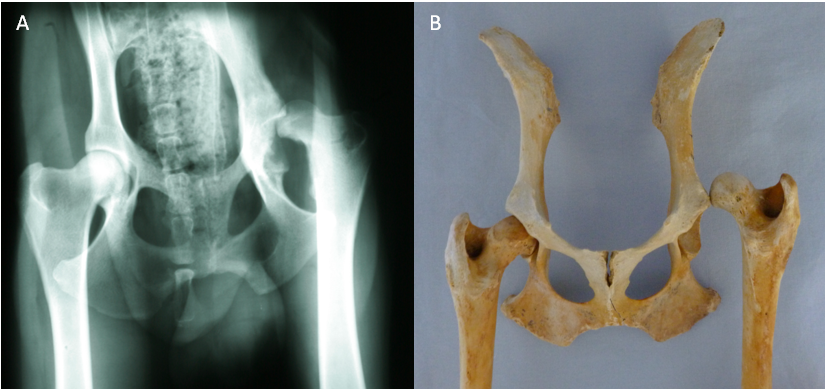

"Tyler", ein Dobermann-Mix, wurde am 18. August 2011 vom Nümbrechter Tierschutzverein "Menschen für Tiere e.V." in der Praxis vorgestellt mit dem Hinweis, er habe große Probleme mit seiner Hüfte und könne nur sehr schlecht laufen. Er war abgemagert bis auf die Knochen, lethargisch und litt sichtbar unter Schmerzen. Tyler zeigte einen deutlichen Muskelabbau und einen Hochstand des rechten Oberschenkels. Bei der Ganguntersuchung ist uns eine starke Lahmheit dieses Beines aufgefallen. Der Bewegungsumfang des Hüftgelenkes war deutlich eingeschränkt und bei der Streckung zeigte der Hund Schmerzen. Daraufhin haben wir eine Röntgenuntersuchung durchgeführt, wobei sich herausstellte, dass die Hüfte luxiert war, mit anderen Worten: der Oberschenkelkopf saß nicht in der richtigen Position. In einer funktionierenden Hüfte sitzt der Oberschenkelkopf in der Pfanne (s. Abb. 1). Bei Tyler saß der Oberschenkelkopf oberhalb der Pfanne. Er wies diese Veränderung seit langer Zeit auf, so dass der Oberschenkelkopf eine Pseudopfanne im Becken gebildet hatte (s. Abb. 2).

Der künstliche Hüftgelenkersatz wird in der Tiermedizin seit mehr als 30 Jahren zur Behandlung von Hüftgelenkerkrankungen und -Traumata verwendet. Im Grunde werden bei diesem Verfahren Oberschenkelkopf und Pfanne durch eine sog. Oberschenkelkopf- und Pfannenprothese ersetzt. Es gibt verschiedene Modelle von Prothesen. Tylers Oberschenkelkopfprothese besteht aus Titan, die Pfanne besitzt eine Außenhülle ebenfalls aus Titan und eine Innenbeschichtung aus Polyäthylen (s. Abb. 3).